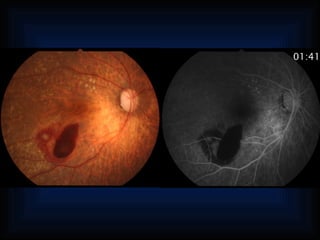

Choroid perfluorescence Retina omalous vessels Subretinal neovascularization Tumorvessels Chorioretinal anastomos Vascular tortuosities Dilation and shunts Anastomosis Neovascularization Aneurysms Teleangiectasia Tumor vessels Hamartoma Neovascularization Tortuosity Optic nerve head Dilation Hamartoma Tumor vessels